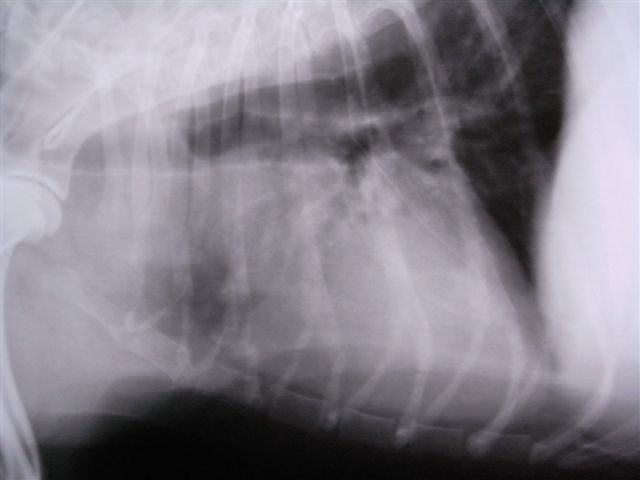

心臓の上部にしこり3cm大が確認できる そのため気管が蛇行している。気管の分岐部より後方は肺炎像がみられる。